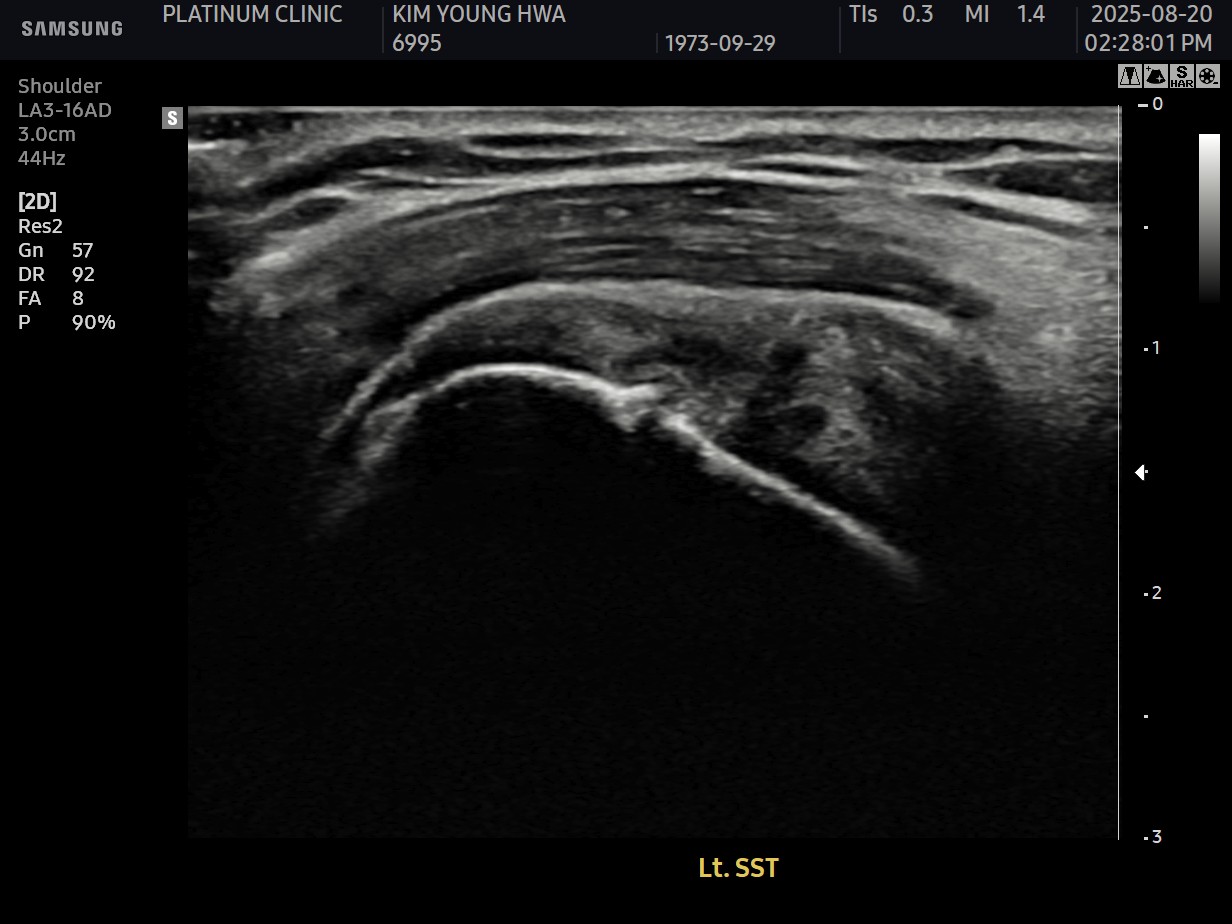

MRI와 초음파 검사 결과:

진단 결과:

- ✓관절면측 부분파열: 약 50%

- ✓점액낭면측 부분파열: 약 35%, 인대 얇아짐 동반

- ✓25년간 반복 사용으로 인한 퇴행성 변화 동반

양쪽 모두 손상된 복합 파열이었습니다.

- ✓관절면측: 봉합 부위 안정적 유지

- ✓점액낭면측: 인대 두께 4.8mm → 6.5mm (1.7mm 증가)